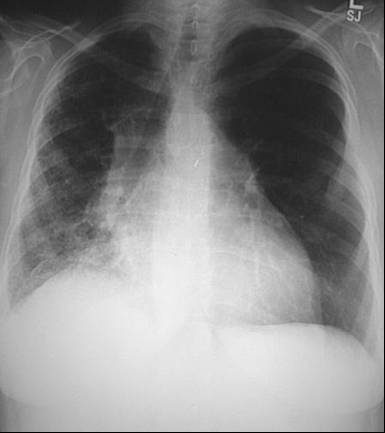

Radiografia toracica

Semnele radiologice. Cordul este marit de volum: diametrul bazal cardiac este mai mare decat jumatatea diametrului transvers bazal pulmonar. Venele pulmonare sunt dilatate. Artera pulmonara principala dreapta este dilatata si ea, la fel si ramura stanga a arterei.

Campurile pulmonare sunt incetosate datorita edemului pulmonar; aceasta tine de mai multe cauze:

• cresterea densitatii interstitiului din zonele centrale pulmonare;

• cresterea densitatii septurilor interlobare, interlobulare si subpleurale (prin aceste zone se face drenajul lichidului transsudat). Acumularea de lichid in spatiile interlobulare produce doua aspecte deosebite, care pot coexista: aspect de linii A. Kerley si de linii B. Kerley, orientate orizontal in zona bazelor; de asemena se constata prezenta de lichid subpleural, de obicei in unghiul costofrenic si bazal, simuland radiologic diafragme ridicate; prezenta de lichid liber in cavitatile mari pleurale (in dreapta in special);

• edemul pulmonar alveolar. Aspectul este "in pete" cu contururi rotunjite; cand conflueaza mai mult zone cu edem, aspectul simuleaza pneumonia, bronhopneumonia, tumoarea sau infarctul pulmonar. O forma mai severa ca prognostic este cea "in fluture";

• mediastinul este rigid;

• venele cava superioara si azygos sunt dilatate.

Examenul radiologic toracic si electrocardiograma pacientului sunt evidentiate

astfel:.

4. Staza pulmonara (raluri crepitante, diminuarea transparentei bazelor pulmonare, preponderent in dreapta pe radigrafia toracica - edem alveolar) secundara insuficientei ventricului stang (zgomot III prezent).